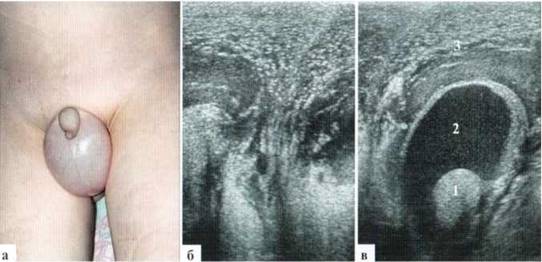

В редких случаях диаметр измененной гидатиты может превышать 10—12 мм и у маленьких детей практически достигать размеров яичка (рис. 2.1.2).

Рис. 2.1.2. Крупные размеры трансформированной гидатиды: 1 — яичко, 2 — гидатида. Размеры яичка и гидатиды практически одинаковы. Сосудистый рисунок при ДДС в гидатиде не прослеживается (б)